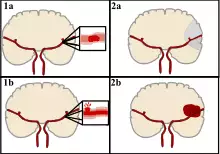

Classification

There are two main categories of strokes. Ischemic (top), typically caused by a blood clot in an artery (1a) resulting in brain death to the affected area (2a). Hemorrhagic (bottom), caused by blood leaking into or around the brain from a ruptured blood vessel (1b) allowing blood to pool in the affected area (2b) thus increasing the pressure on the brain.

Strokes can be classified into two major categories: ischemic and hemorrhagic.[18] Ischemic strokes are caused by interruption of the blood supply to the brain, while hemorrhagic strokes result from the rupture of a blood vessel or an abnormal vascular structure. About 87% of strokes are ischemic, the rest being hemorrhagic. Bleeding can develop inside areas of ischemia, a condition known as "hemorrhagic transformation." It is unknown how many hemorrhagic strokes actually start as ischemic strokes.[2]